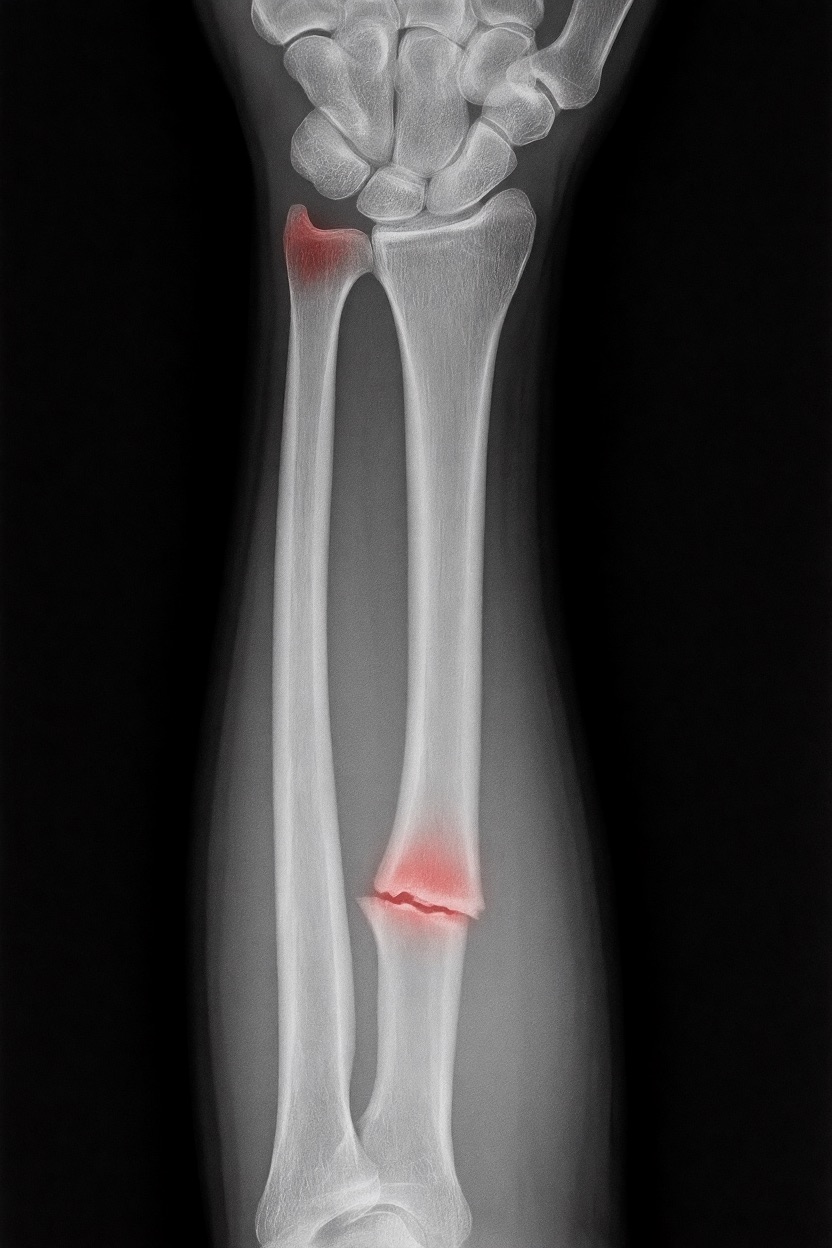

アートや写真の編集用に設計されたFlux Kontextのようなモデルを、医療画像、たとえば「単純な」骨折の赤色マーキングに使用できるか?

即答:面白い結果を出すが、過剰に反応し、医療ツールとしては信頼性に欠ける。これはアイデアを試すためのプロトタイプに過ぎない。

さらに攻撃的な設定(例:rk beta57、Denoise 1.0)では、**偽陽性100%、検出100%**という馬鹿げた結果に:すべてを赤で塗りつぶし、健常部もほぼすべて骨折と誤認する。未経験の目には区別がつかない。

有効な用途

- 医療画像におけるAIプロトタイプやテスト

- X線の「疑わしい」領域を視覚的に目立たせる(実験的・創造的アート、エキゾチックなツール xD)

- 感度 vs 偽陽性のバランスを実験するための教育的・実験的素材

不適切な用途

- 重大な診断には使用しない

- 医師の代わりにはならない、まったくもって!

このLoRaは視覚的実験用のみです。

医療機器ではありません。信頼性がなく、臨床診断には使用しないでください。

もちろん、このツールはオープンソースで、高速(1回の分析に25秒)、一般のデスクトップPCで動作するため、今後このコンセプトをさらに実験する価値はあると思います…今後の展開に注目です!